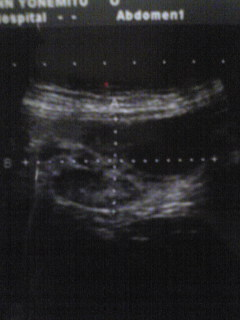

【8月22日】: 治療開始して1ヶ月、掛かり付けの病院で再診を受けました。

腫瘍の大きさ:15,1mm × 31,2mm・・・全体としては半分になっています。